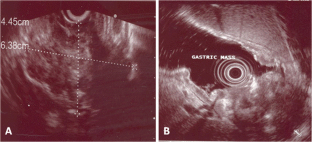

Fig. 3